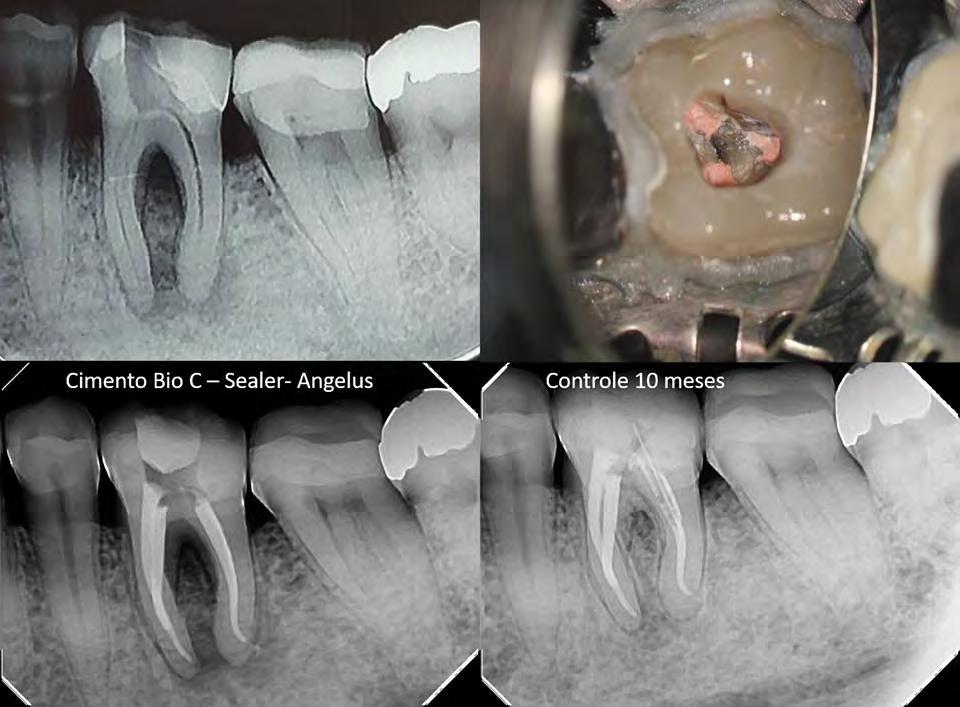

Prof. Dr. Warley Tavares

04/2017

Masculino

45 años

Periodontitis Apical Crónica.

O. 10 meses

Instrumentación con NiTi, Hipoclorito de Sodio 2,5%, medicación con Hidróxido de Calcio por 10 días.

Obturación con gutta percha y BIO-C® SEALER.

02/2018